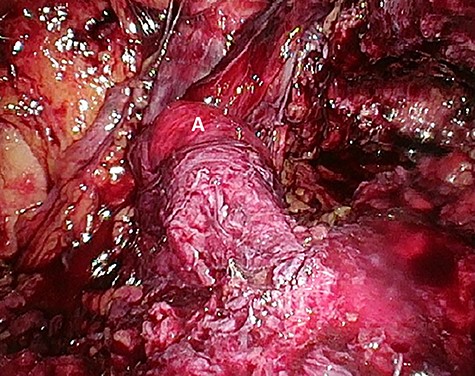

Considering the patients’ comorbidities (obesity, Type 2 diabetes mellitus), a re-TAPP was performed to avoid possible wound complications. The recurrent hernia was presumably confirmed as a lateral inguinal hernia. After dissecting dense fibrotic scar tissue around the previous mesh preperitoneally, the hernia sac was released. A large spermatic cord lipoma was found and dissected (Figs 1 and 2). A new mesh (BARD® 3D Light Mesh, 10 × 15 cm) was inserted.

Suspected indirect inguinal recurrence hernia with a large spermatic cord lipoma (A), epigastric vessels (B), ductus deferens (C), peritoneum with previous mesh (D).